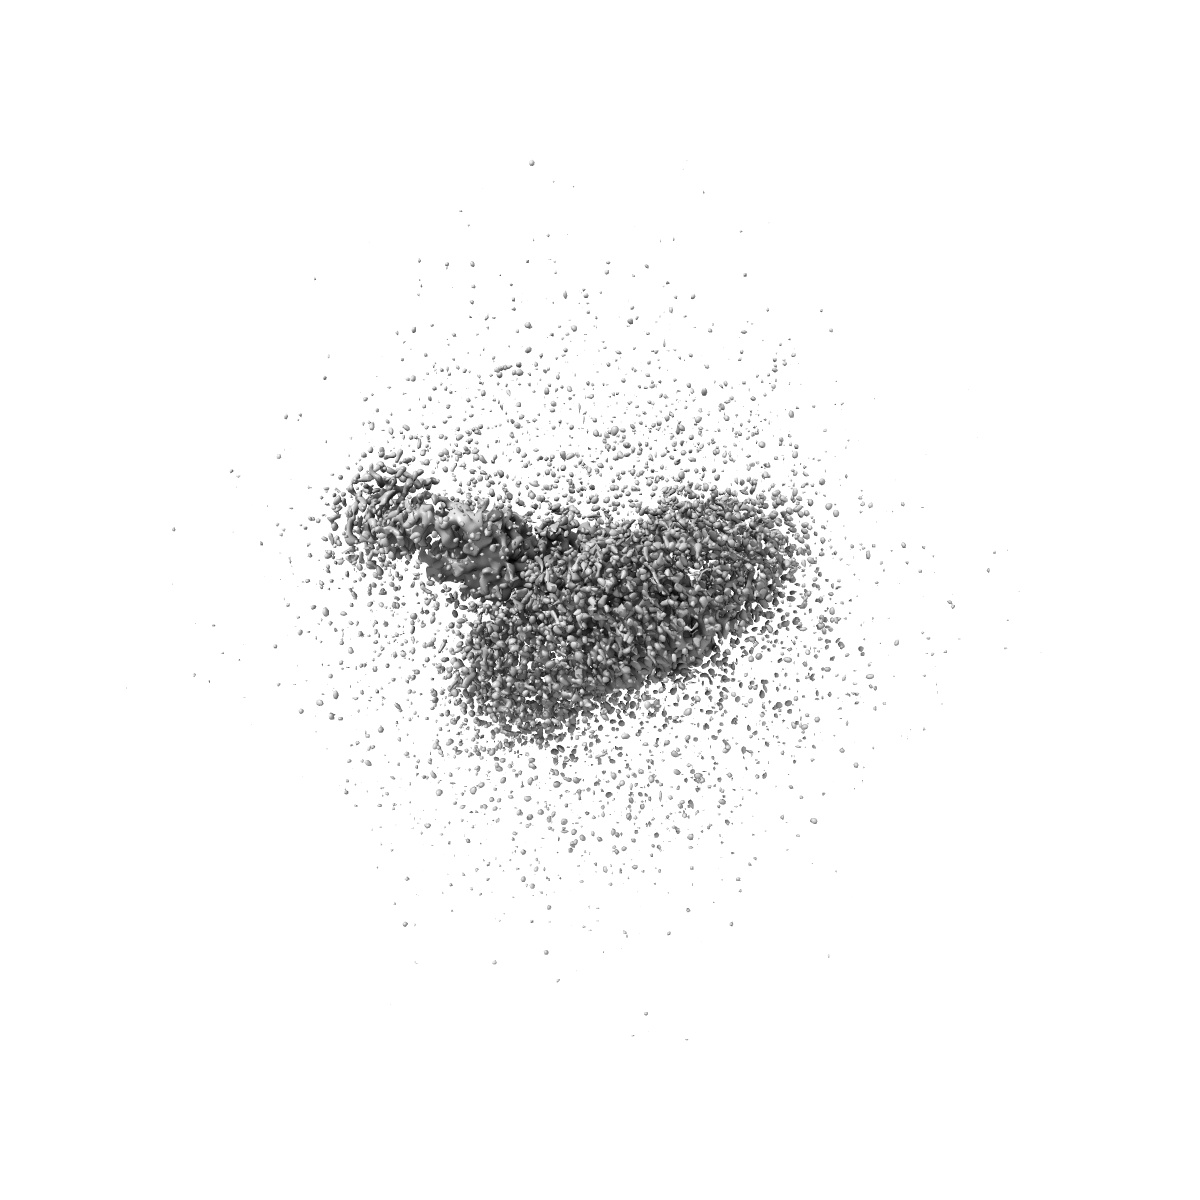

Cryo-EM Structure of the wild-type human serotonin transporter in complex with ibogaine and 15B8 Fab in the inward conformation

Sample Organism: Mus musculus, Homo sapiens

Sample: Human serotonin transporter in complex with Fab bound to ibogaine

Fitted models: 6dzz

Serotonin transporter-ibogaine complexes illuminate mechanisms of inhibition and transport.

Coleman JA, Yang D, Zhao Z , Wen PC , Yoshioka C, Tajkhorshid E, Gouaux E

(2019) Nature , 569 , 141 - 145